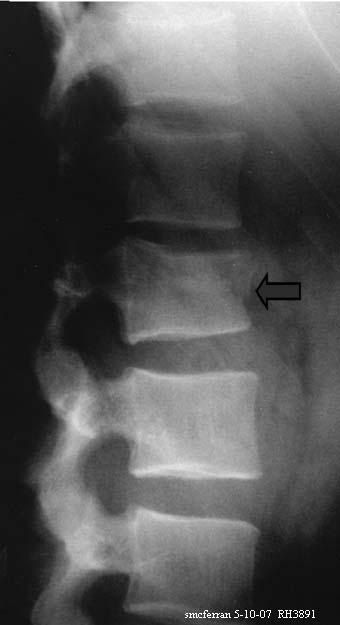

Got the all clear to go back to work after 4 months in a cast. I compressed my L1 vertebrate, back in September by fall 18ft out of a tree.

19 years ago i had a wedge fracture L1 L2 a lot worse than yours i was 1/2" of been paralised

The doc did said it will me haunt later on in life. I know i only wedge on of my vertebrates but when you loss the power of your legs for two days it was scary. Something to with pressure on my spinal cord.